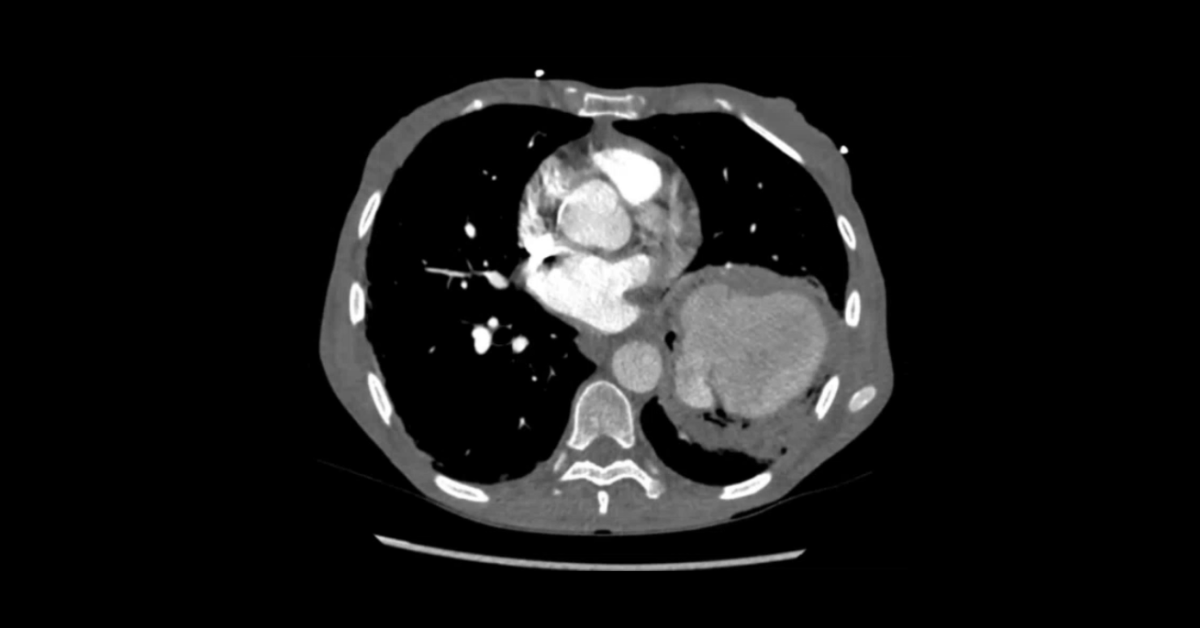

Acute Pulmonary Presentations Part 4: Pulmonary Arteries

A collection of pulmonary CT cases demonstrating a variety of emergency pulmonary presentations.

2. Describe the various appearances of pulmonary artery aneurysms.